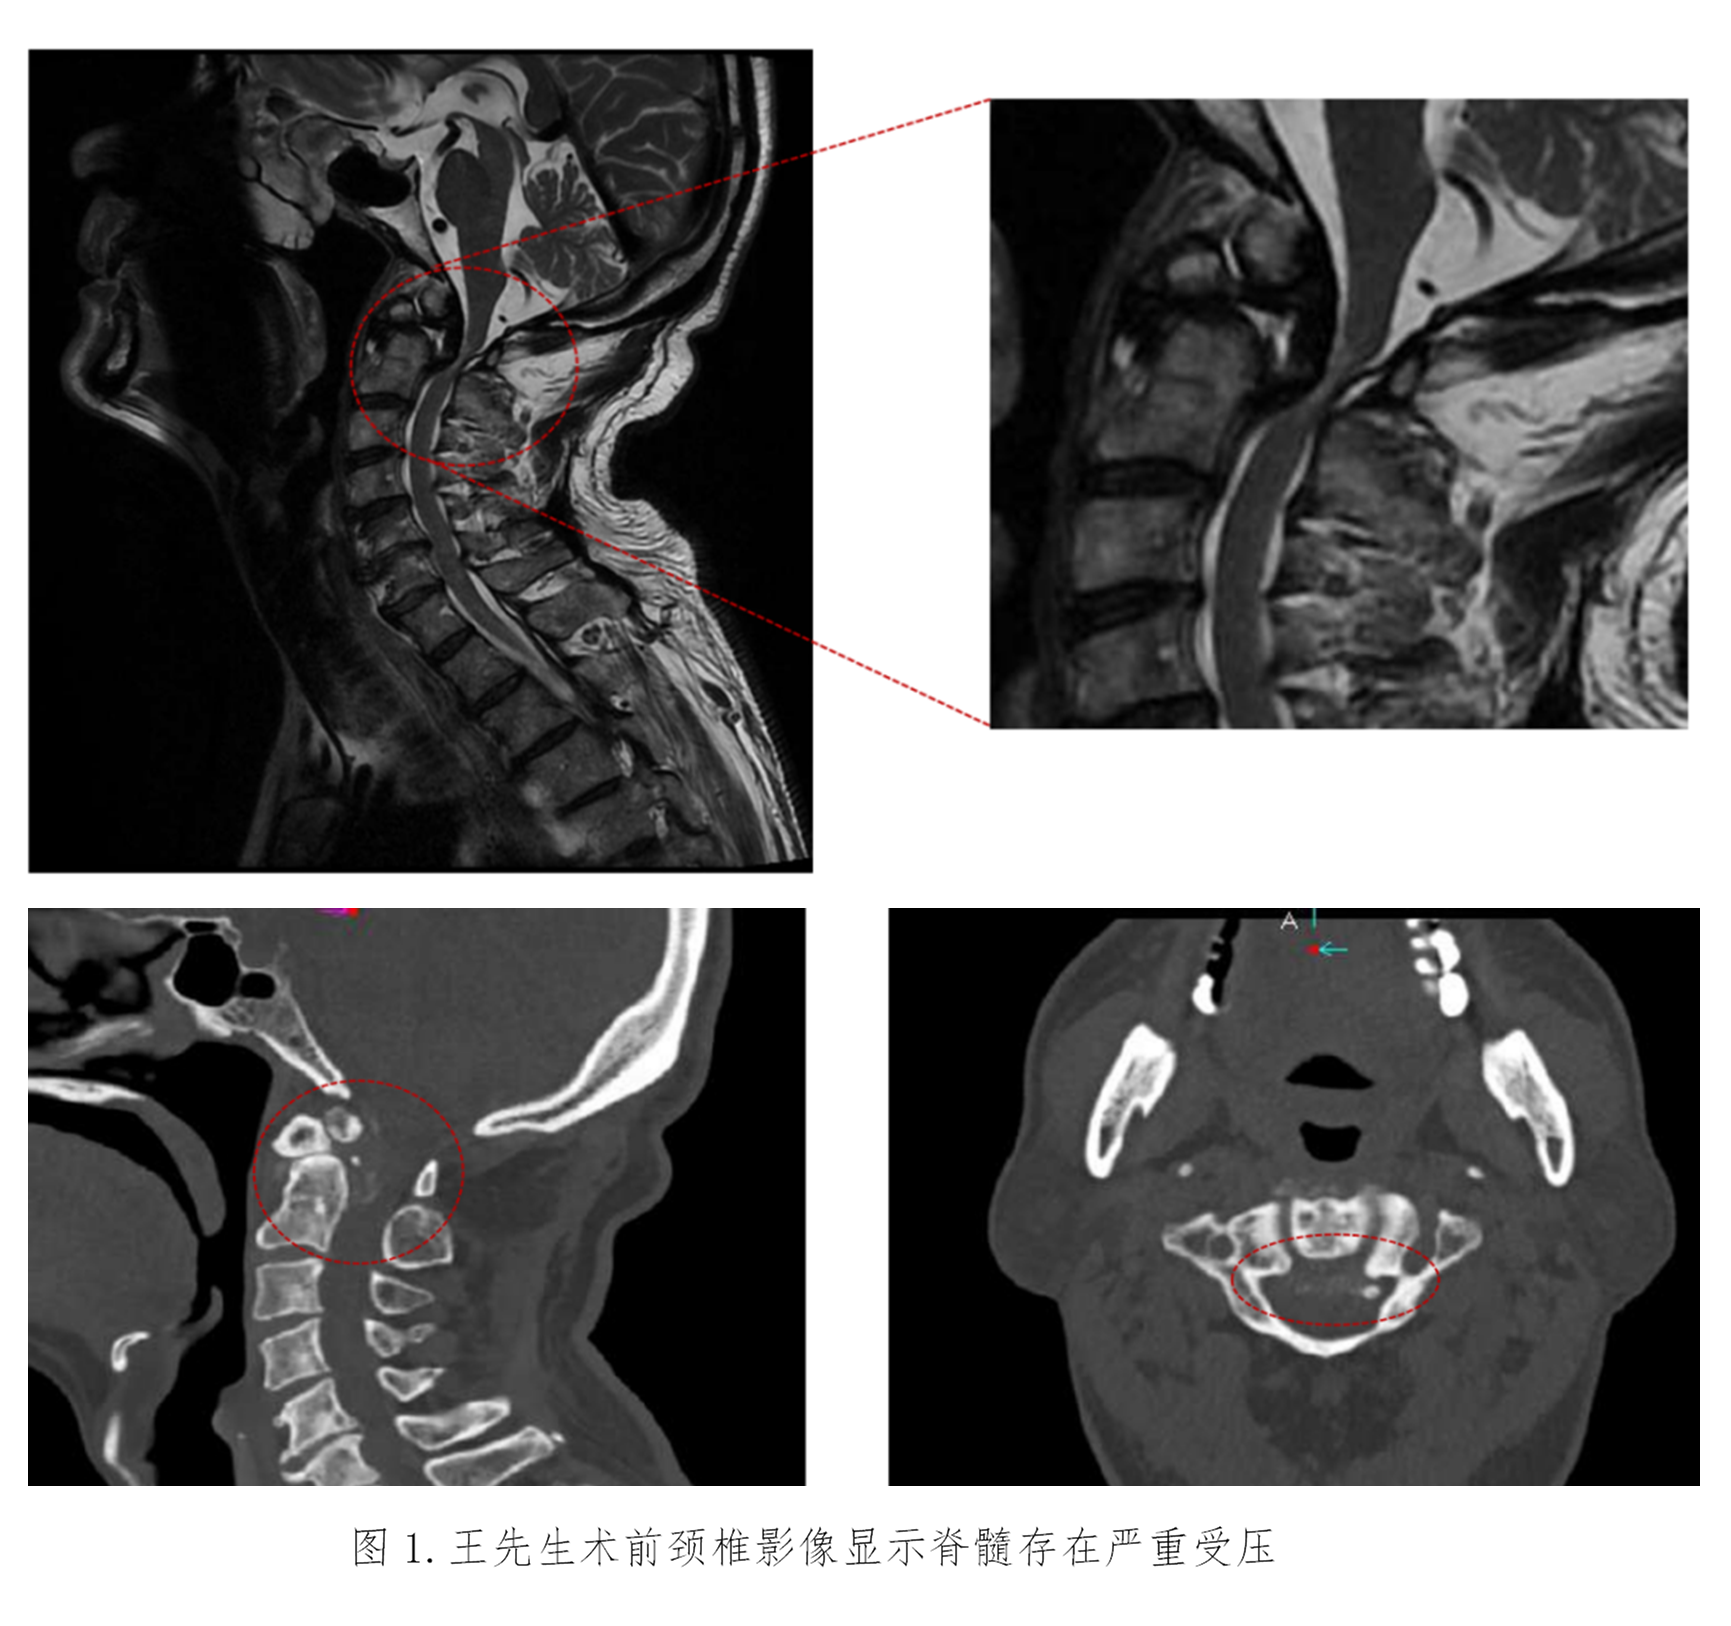

患者王先生已72岁,四肢乏力进行性加重10年,伴左下肢跛行4年,因担心需要手术治疗而没有正规就医。近期已无法独立行走,经推荐来到苏大附四院姜为民主任门诊就医。王先生的查体结果表现出明显的高位脊髓损伤症状:左上肢肌力下降至4级,左侧霍夫曼征、踝阵挛及巴彬斯基征均为阳性,左足下垂;右侧病情稍轻。影像学检查显示“游离齿状突畸形”——即第二颈椎(C2)齿状突发育异常并游离,后缘异常增生导致上段颈髓严重受压,脊髓功能受损使得患者近年来行走能力不断下降,并因此频繁跌倒,这对患者的生命安全构成了极大威胁。